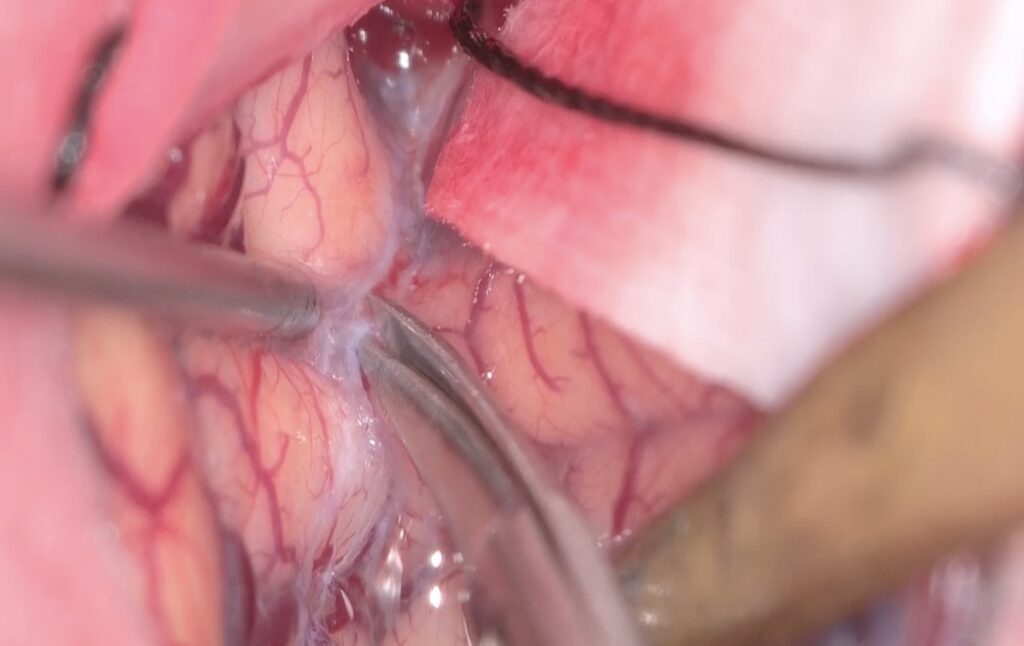

Trans-lamina terminalis approach、何度もやった古典的なアプローチです。A2と伴奏し縦走する視床下部動脈を温存して、その間隙から腫瘍を減圧していきます。

腫瘍を減圧し、最後に起こして、中脳水道や脳底動脈を確認しました。視交差の下は減圧にとどめました。